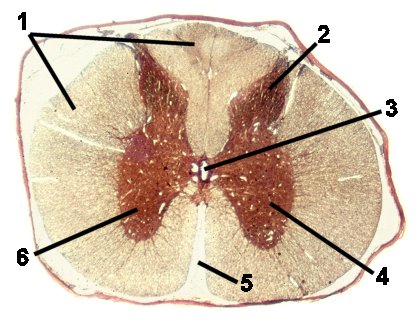

A very low magnification of the spinal column demonstrating the different structures.

Fig 026-008 |